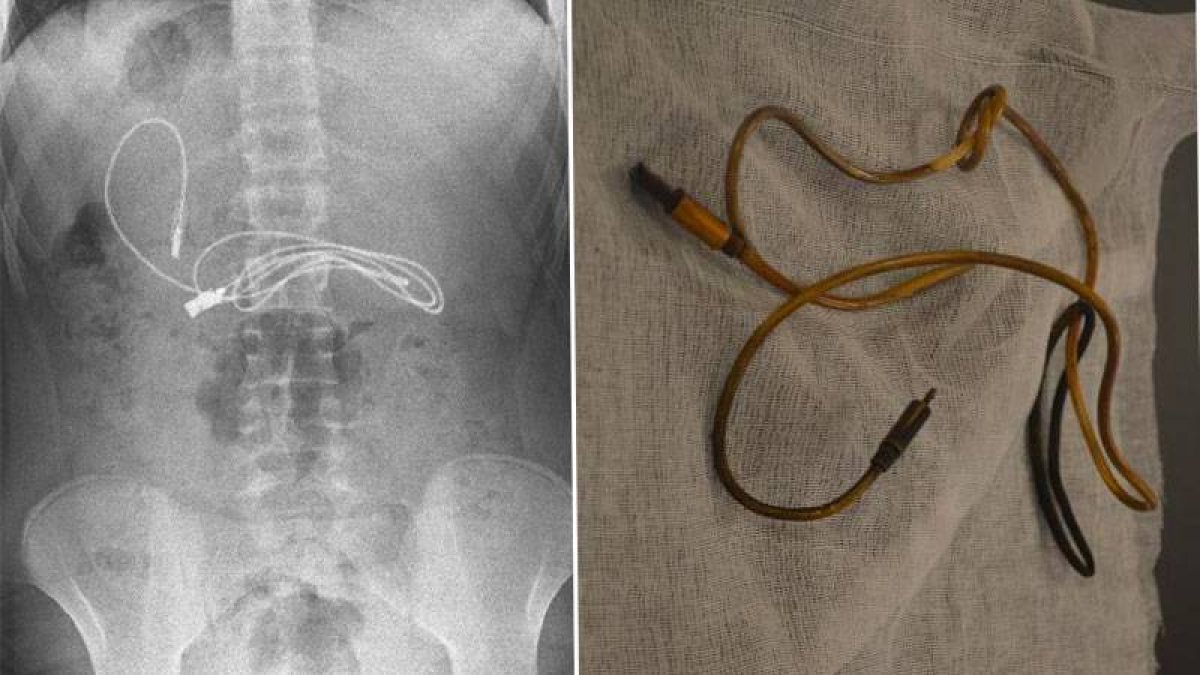

Diyarbakır'da kusma ve bulantı şikayetiyle ailesinin hastaneye götürdüğü 15 yaşındaki çocuğun midesinden çıkanlar şoke etti. Çocuğun mide röntgeninde şarj kablosu ve toka olduğu tespit edildi.

Ambulans ile Fırat Üniversitesi Hastanesi'ne sevk edildi. Üniversitenin Çocuk Gastroenteroloji Hepatoloji ve Beslenme Bilim Dalı Başkanı Prof. Dr. Yaşar Doğan ve ekibi tarafından yapılan endoskopik işlemle çocuğun midesindeki kablo ve toka başarıyla çıkarıldı. Tedavisinin ardından sağlığına kavuşan çocuk taburcu edildi.

Ameliyatı gerçekleştiren Prof. Dr. Yaşar Doğan, kablonun bir ucunun ince bağırsağa geçmesi nedeniyle zorlandıklarını ifade ederek, şöyle konuştu:

“Hastanın kusma ve karın ağrısı şikayetleri olması üzerine sağlık kuruluşuna başvurulmuş. Orada yapılan incelemelerde hastanın midesinde kablo tespit edilmesi üzerine bize danışıldı. 112 aracılığıyla hastaya gerekli işlemi yapıp yapmayacaklarını bize sordular. Biz de hastayı bize gönderebileceklerini kendilerine ilettik. Hasta bize geldikten sonra ön hazırlık yapıldı ve gerekli olan açlık süresinin ardından hastaya endoskopik işlem yapıldı. Endoskopik işlemle midedeki kablo çıkarıldı. Kabloyu çıkarırken açıkçası zorlandık, çünkü kablonun bir ucu ince bağırsağa geçmişti. İşlem başarılı bir şekilde sonlandırıldıktan sonra hasta sağlıklı bir şekilde evine gönderildi.”